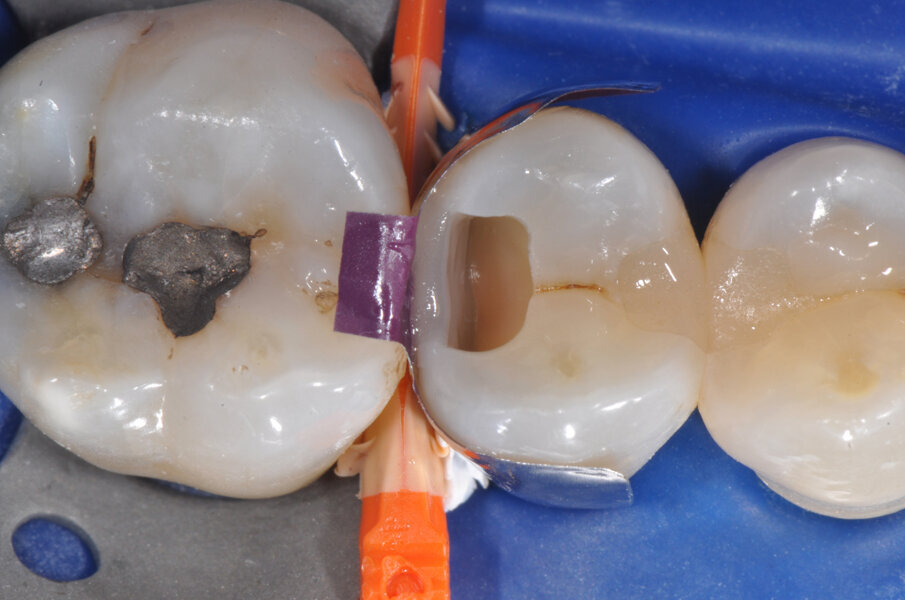

Il caso riguarda l’esecuzione di un restauro interprossimale col sistema di matrici sezionali anelli separatori e cunei Composi-Tight 3D Fusion. Il paziente presenta carie penetrante (D3) a carico dell’elemento 1.5 distale. Viene posizionata la diga di gomma (Fig. 1).

Viene posizionato un cuneo con matrice allo scopo di proteggere il dente aprossimale (Fig. 2). La cavità è stata preparata, la carie asportata, i margini cavitari devono essere rifiniti (Fig. 3). Vengono rimossi il cuneo e la matrice per meglio rifinire il gradino cervicale e per valutare che tipo di cuneo utilizzare (Fig. 4). Ai fini di migliorare l’adattamento della matrice viene utilizzata una striscia abrasiva in plastica di grana media (Fig. 5).